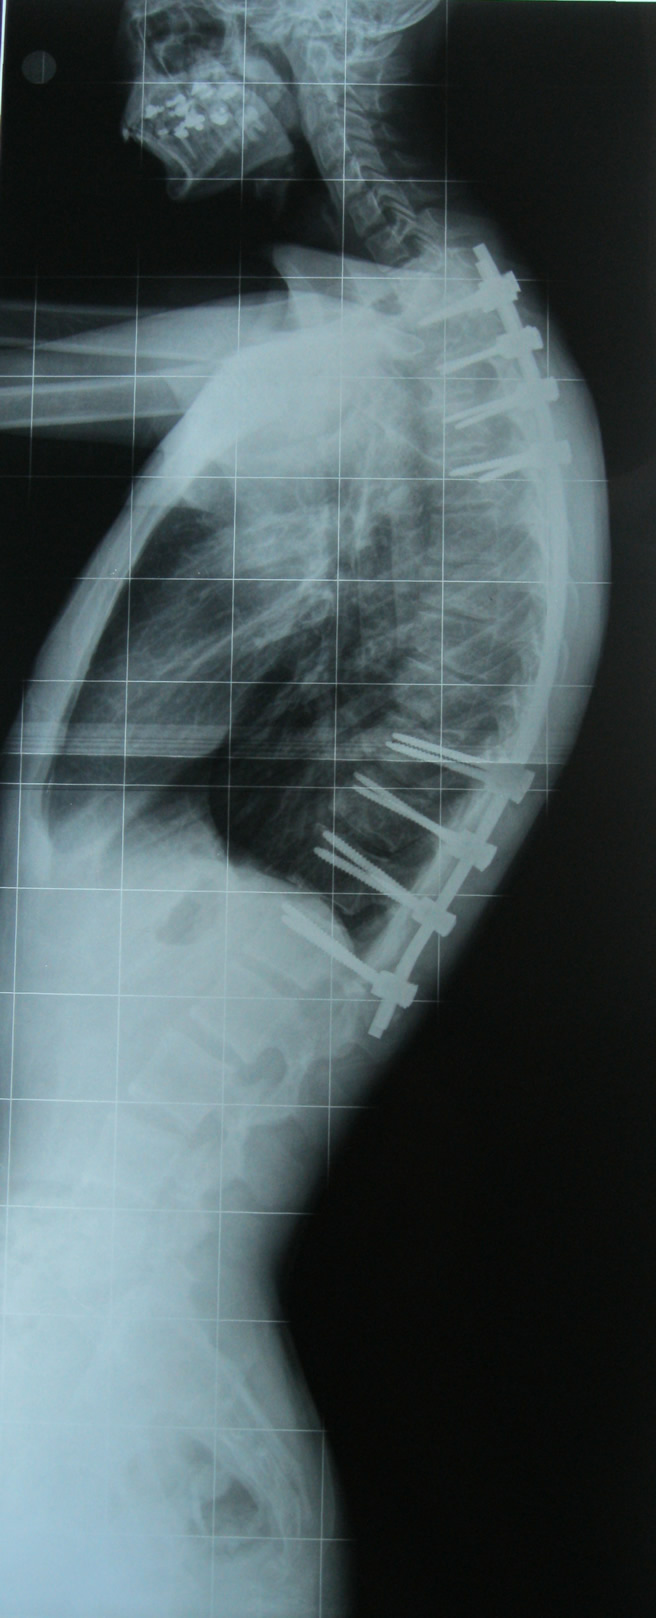

Scheuermann kifozu olan bir hastanın ameliyat öncesi ve sonrası fotoğrafı görülüyor.